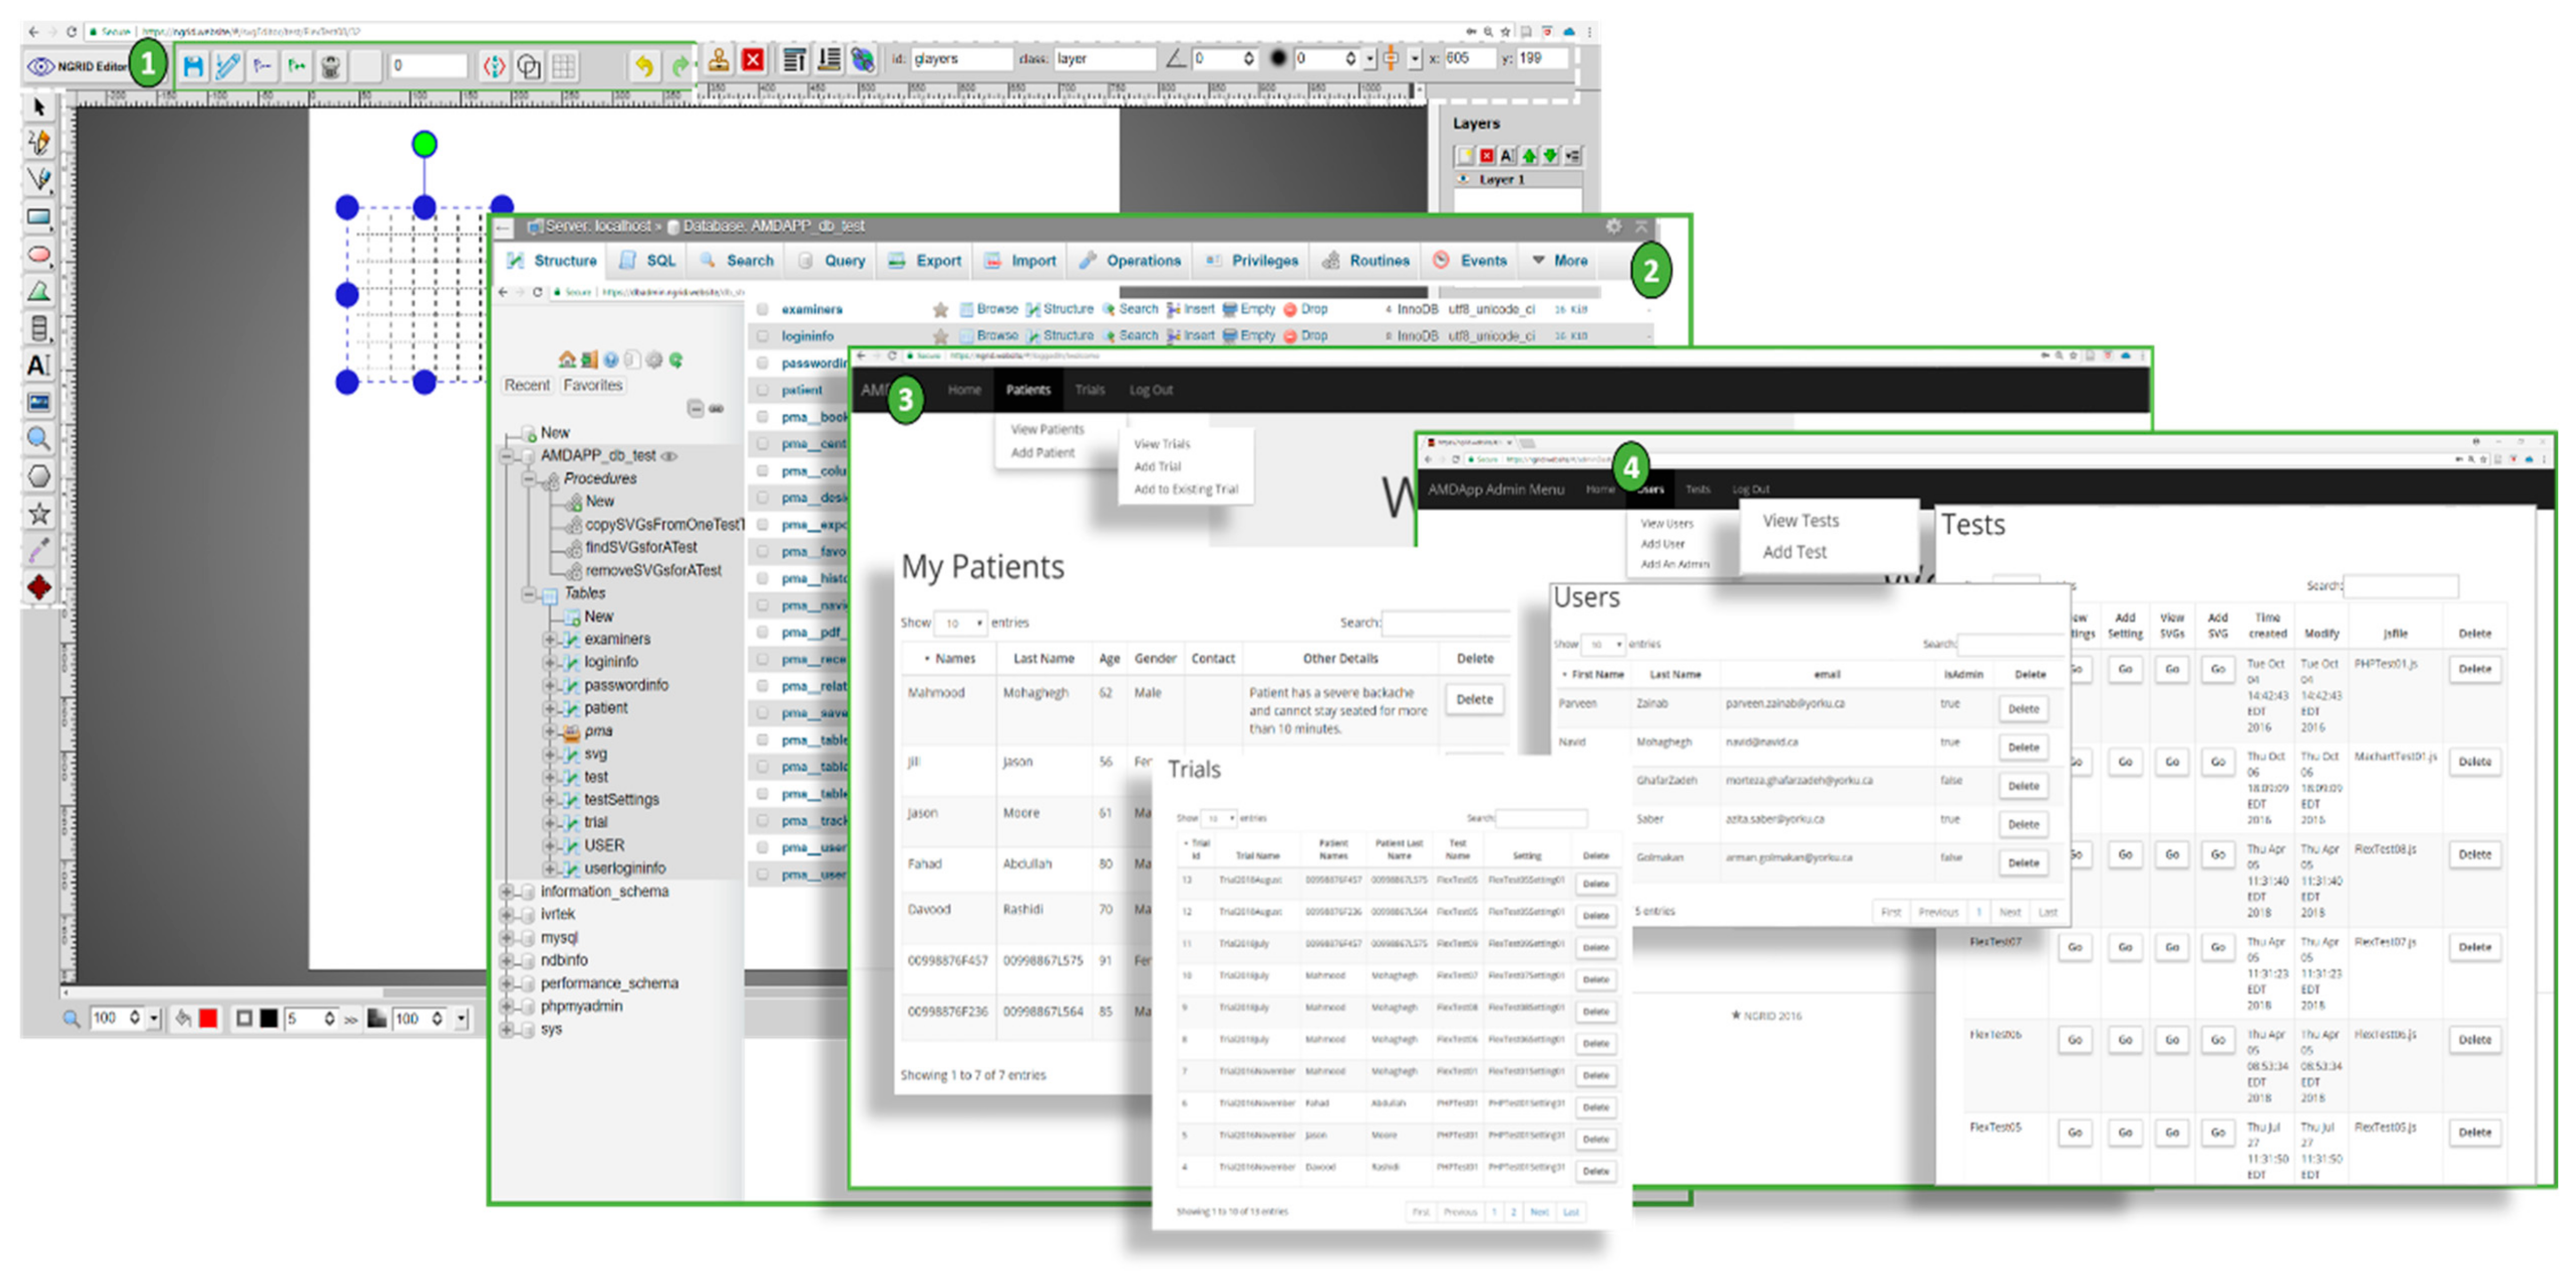

4.2.1. NGRID VD Test and SVG VD Test Editor

4.2.2. Admin Interface

4.3. Heatmap Generator

4.4. Other Programs

| Program | Language | Input/Process/Output |

|---|---|---|

| VD Test | C++ and C# | Consumes stored VD tests patterns from online admin interface and produces raw test results stored in the cloud data center cluster. |

| SVG VD Test Editor | HTML5, CSS3 and Javascript | Facilitates creating various SVGs that compose patterns used in tests. The outputs are stored in database |

| Admin Interface | Scala, Java, HTML5/CSS3 and Javascript | An online website that allows physicians and admins to login and manage various patients and control a different aspect of the VD test. |

| Heatmap Generator and Analyzer | R, Python, C#, C++, OpenCV, HTML5, CSS3 and Javascript | Consumes raw VD test results along with various rasterization and image processing techniques to produce heatmap results for a test that a patient has completed. |

| Database | SQL and NoSQL | A highly available database within datacenter that keeps all test data, hashed credentials and test results. |